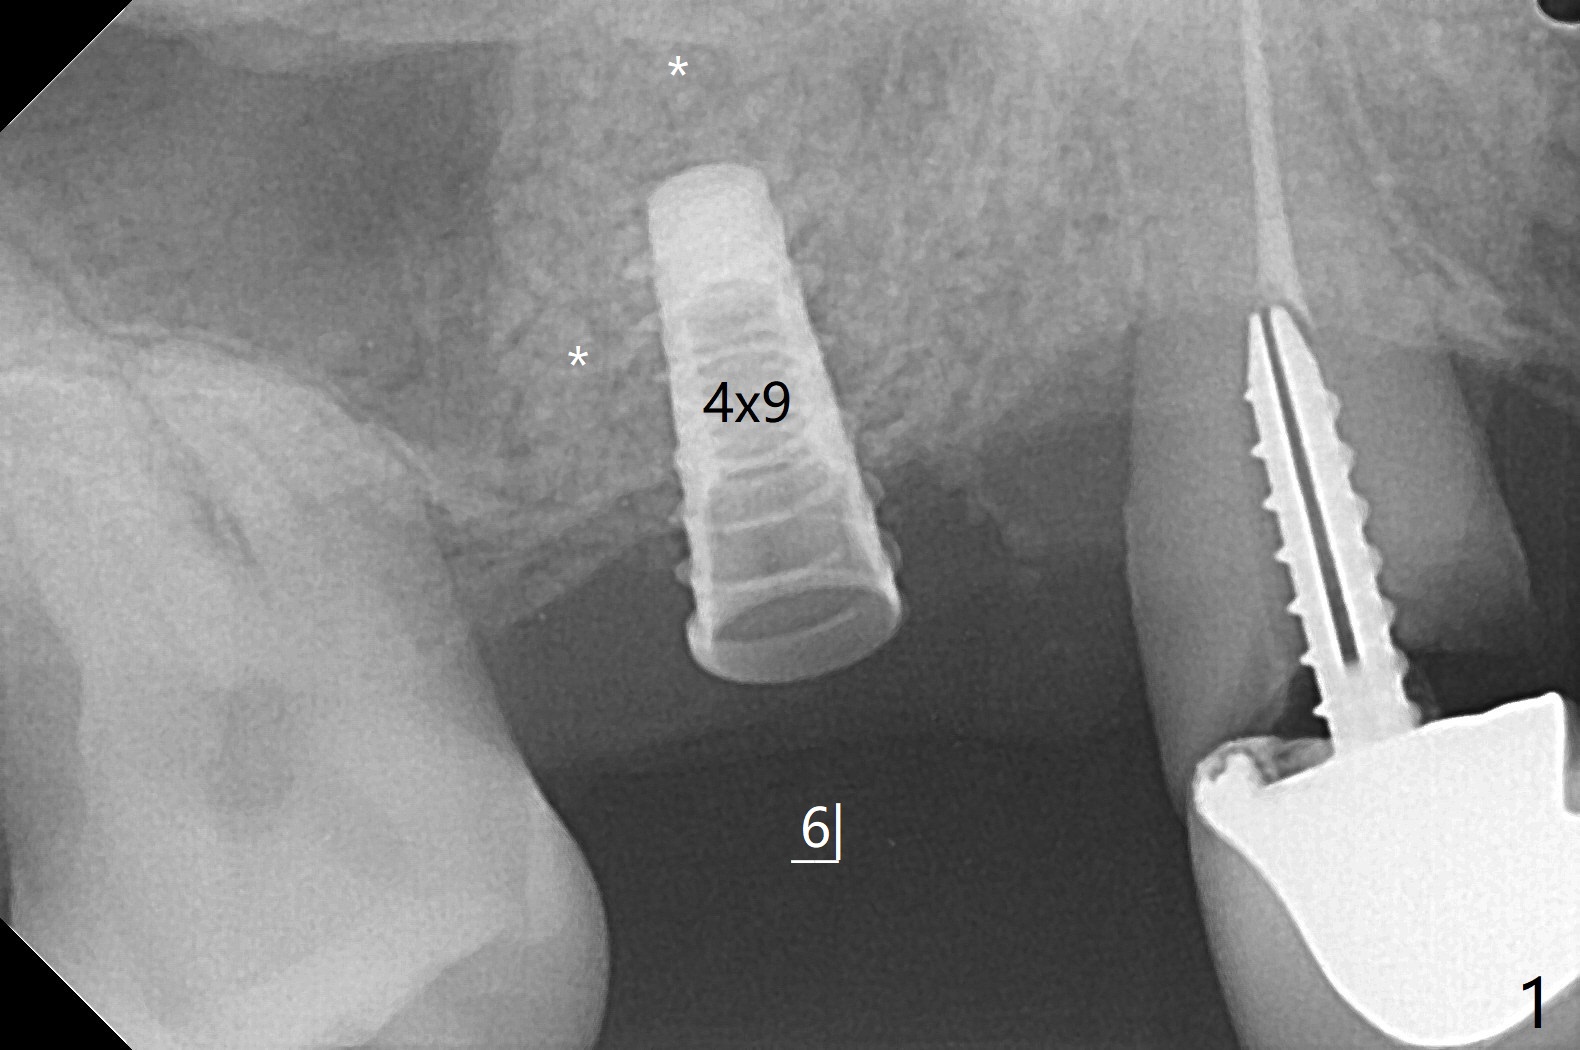

49岁女(个子小)牙齿问题多,同意先做右上5,6种植,6骨质高度1-2毫米,一个月前因动脉出血外提升失败。今天她回来做内提升,同意如果条件合适,同期徒手植牙(将来做一个磨牙牙冠),事先服用阿奇霉素。使用粘性骨粉和报废植体做内提(图一:*),最后植入4x7毫米植体(35Ncm),近中颊侧平牙槽嵴(图二:*),其余骨上 (图三: *),不敢植入太深,怕掉入上颌窦。第二个预防掉入上颌窦措施是利用大号基台(图三),然后在基台周围放置骨粉(图四:*,五),缝合,牙周敷料。伤口愈合后,准备制作树脂敷料,防止植体和基台往口腔脱落。术后五天复诊,无上颌窦炎症,牙周敷料稳定。她再回来时已经术后4.5个月,植体稳定,更换基台没有疼痛(图六,七),口腔卫生极佳,使用水牙线,不敢患侧刷牙。